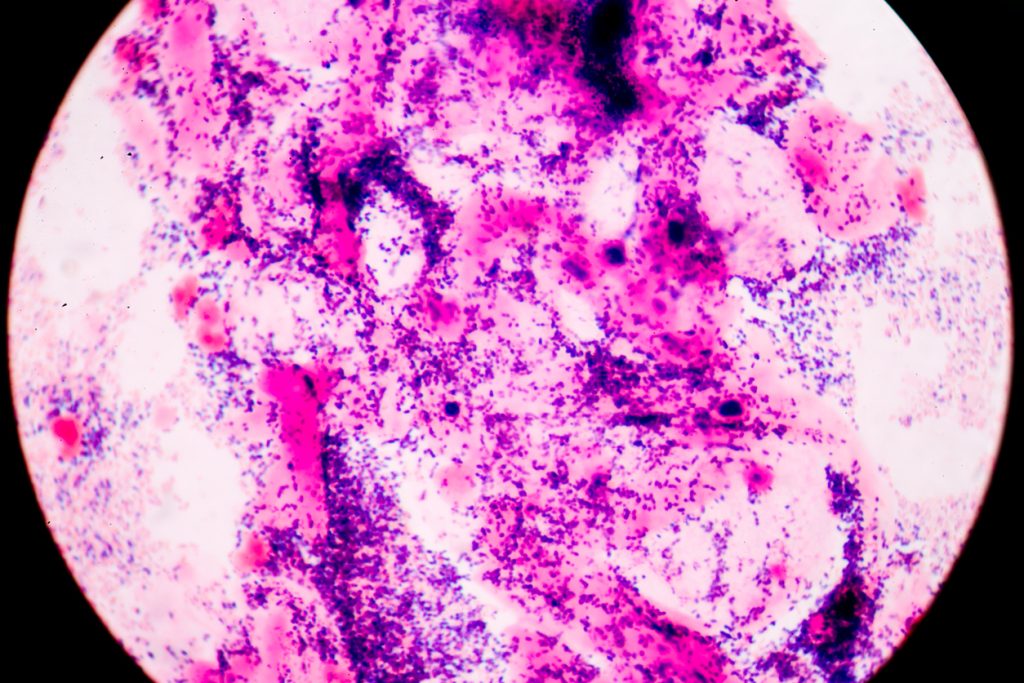

Gram staining, also called Gram's method, is a method of differentiating bacterial species into two large groups (Gram-positive and Gram-negative).